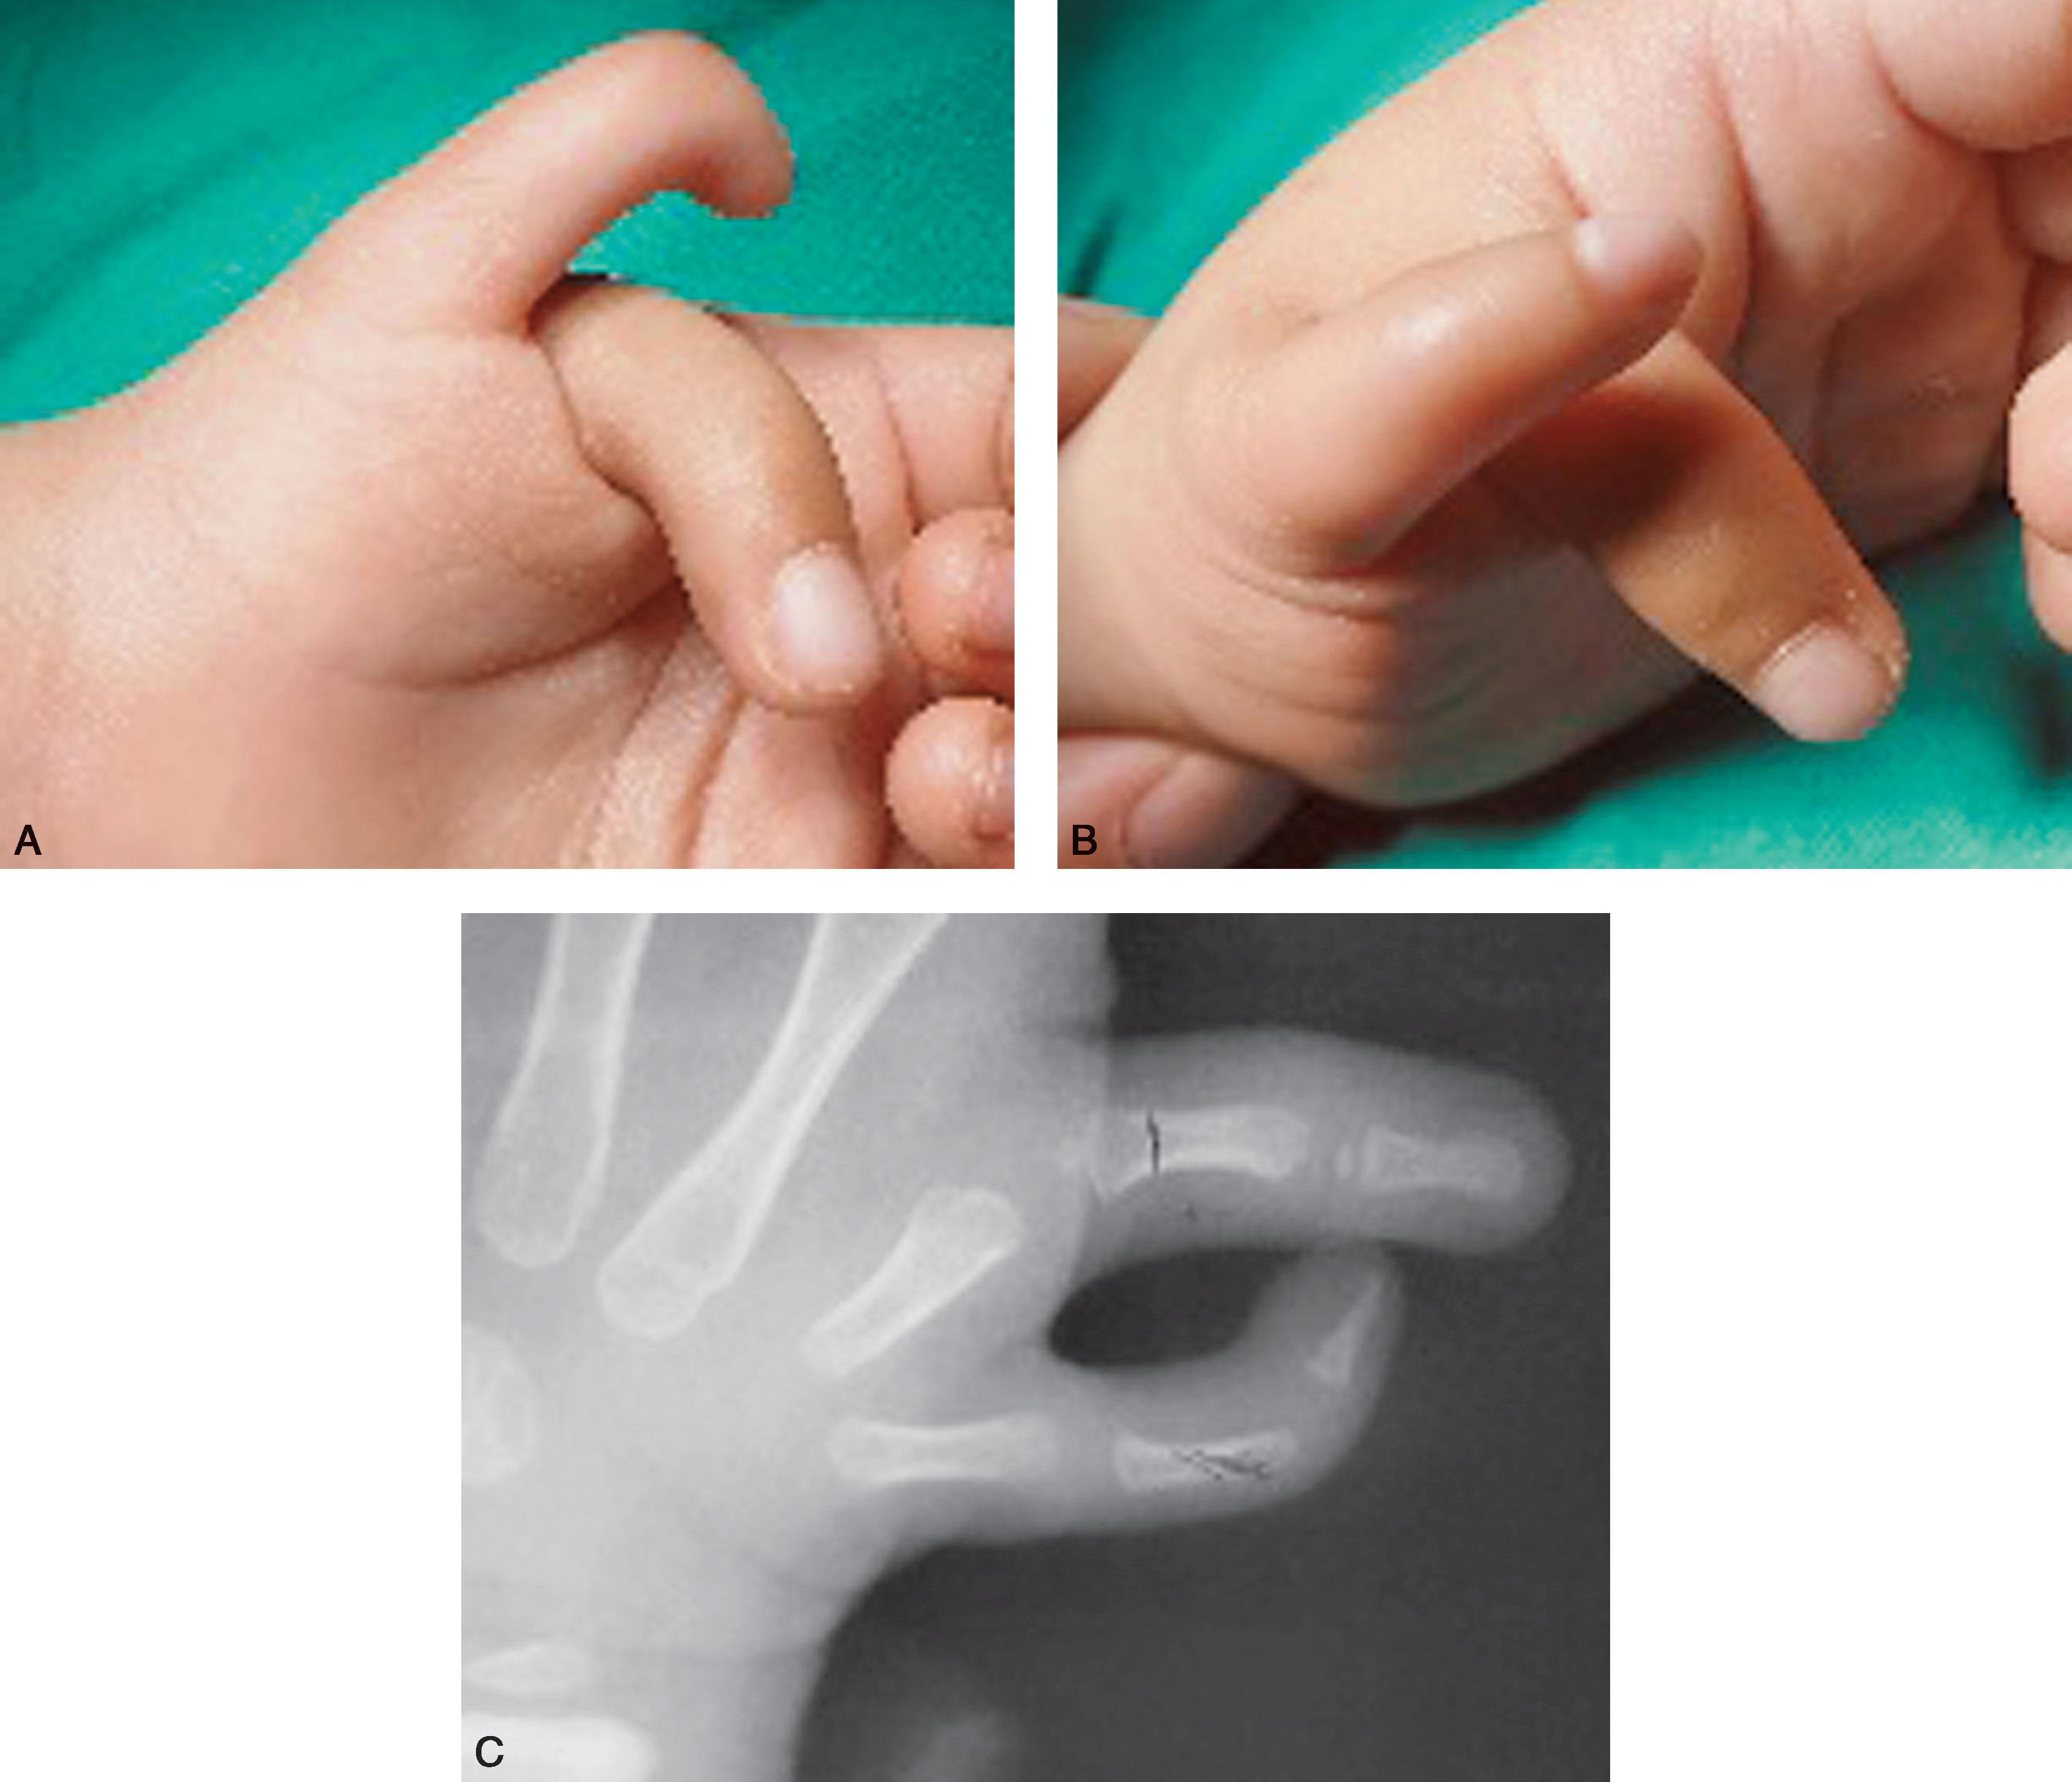

图2-1-15 Ⅲ型病例4

A.右拇指多指,主、次拇指相互交叉,提示各自的拇长屈肌腱止点偏移,即桡侧拇指指屈肌腱偏尺侧,尺侧拇指指屈肌腱偏桡侧,保留的拇指需行肌腱止点移位;B.X 线片提示可选择切除桡侧拇指,但保留尺侧拇指需行拇长屈肌腱止点尺侧移位重建,或桡侧拇指拇长屈肌腱止点缝合固定在保留的尺侧拇指远节基底尺掌侧,以确保保留其指间关节应力平衡,减少偏斜复发

图2-1-16 Ⅲ型病例5

A.左手“蟹爪”样多拇指,桡侧拇指较小;B.X 线片显示分离的近节指骨共用一个宽阔的骨骺,选择切除桡侧拇指及其对应的骨骺,保留的尺侧拇指近节指骨基底,楔形截骨纠正尺偏畸形。 掌指关节向桡侧复位、指间关节复位,同时行关节囊和侧副韧带紧缩。 拇长屈肌腱止点向尺侧移位进行止点重建,或桡侧拇指拇长屈肌腱止点缝合固定在保留的尺侧拇指远节基底尺掌侧,成人可考虑指间关节融合,此例拇指蹼狭小,二期仍需重建